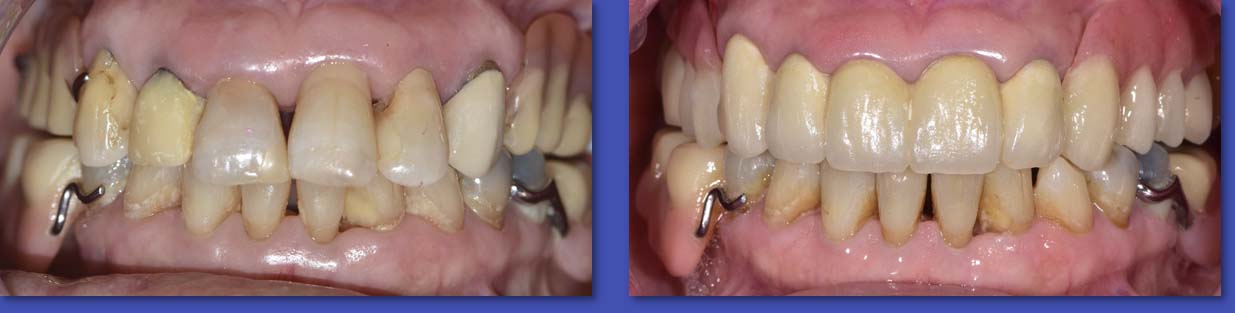

6. PRÓTESIS REMOVIBLES

La prótesis removible es uno de los tratamientos para reemplazar dientes perdidos, puede ser parcial o total de acuerdo a los dientes que reemplaza, y como su nombre lo indica es removible o sea se debe sacar de la boca para realizar las maniobras de higiene bucal y limpieza de la prótesis.

ANTES

DESPUÉS